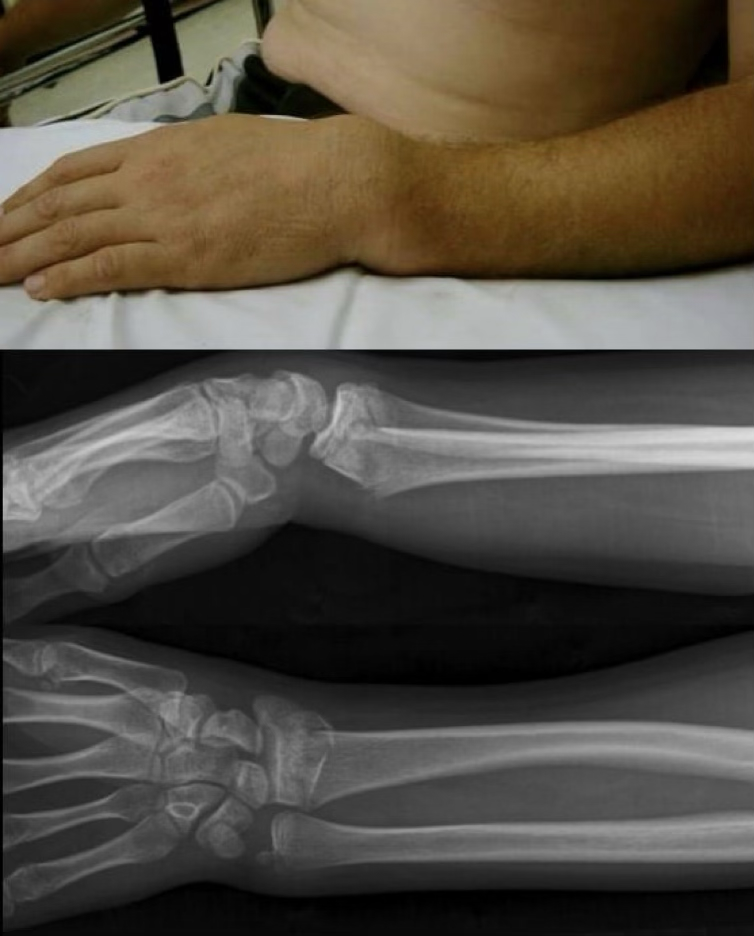

colles fx

radius & ulna fracture where they hyperextend (go dorsally)

smith fx

radius & ulna fracture and hyperflex (go volarly)

forearm fractures

FOOSH or direct blows

super common in youth due to the MOI, but rare to see as ulanr and radial fractures simultaneously

symptoms: pop, pain, swelling, possible deformity, lack of ROM

treatment: splint and ship, will need cast or surgery. 4-8 weeks and then therapy